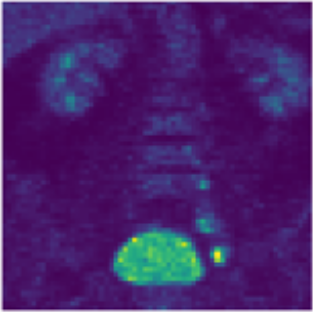

PET-Disentangler: PET Lesion Segmentation via Disentangled Healthy and Disease Feature Representations

Tanya Gatsak, Kumar Abhishek, Hanene Ben Yedder, Saeid Asgari Taghanaki, Ghassan Hamarneh

The Society of Nuclear Medicine and Molecular Imaging (SNMMI) Annual Meeting, 2024 We propose PET-Disentangler, a deep learning method that disentangles PET images into disease and healthy anatomical features to improve lesion segmentation accuracy and outperforms standard 3D UNet models. [Abstract] [BibTeX] [Poster]

Data augmentation (DA), an effective regularization technique, generates training samples to enhance the diversity of data and the richness of label information for training modern deep learning models. mixup, a popular recent DA method, augments training datasets with convex combinations of original samples pairs, but can generate undesirable samples, with data being sampled off the manifold and with incorrect labels. In this work, we propose ζ-mixup, a generalization of mixup with provably and demonstrably desirable properties that allows for convex combinations of N ≥ 2 samples, thus leading to more realistic and diverse outputs that incorporate information from N original samples using a p-series interpolant. We show that, compared to mixup, ζ-mixup better preserves the intrinsic dimensionality of the original datasets, a desirable property for training generalizable models, and is at least as fast as mixup. Evaluation on several natural and medical image datasets shows that ζ-mixup outperforms mixup, CutMix, and traditional DA methods.